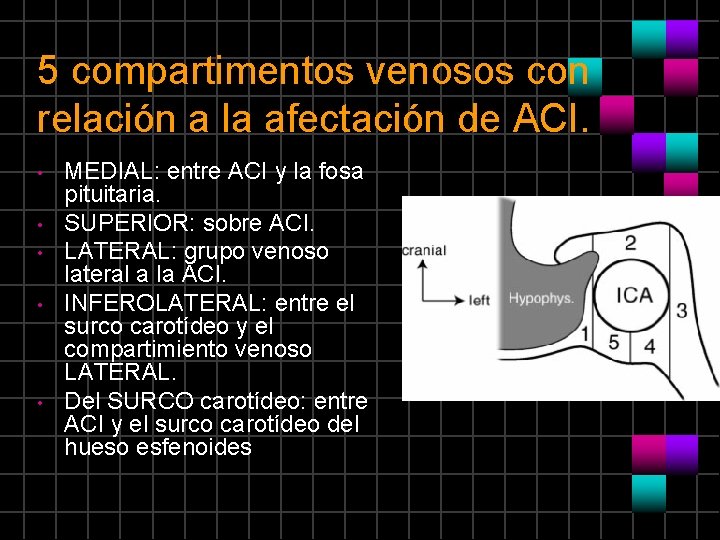

5 compartimentos venosos con relación a la afectación de ACI. • • • MEDIAL: entre ACI y la fosa pituitaria. SUPERIOR: sobre ACI. LATERAL: grupo venoso lateral a la ACI. INFEROLATERAL: entre el surco carotídeo y el compartimiento venoso LATERAL. Del SURCO carotídeo: entre ACI y el surco carotídeo del hueso esfenoides